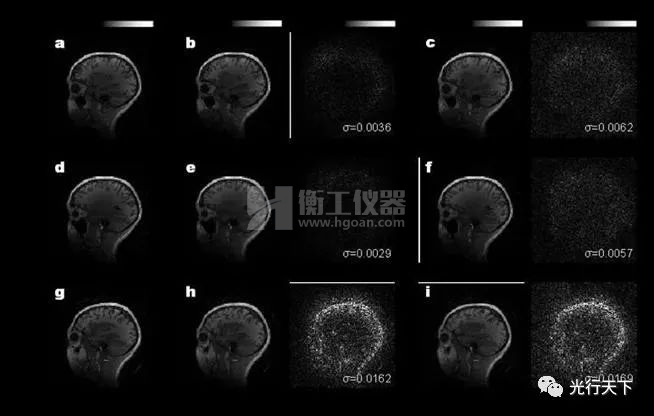

光學(xué)相干點(diǎn)積核芯片重構(gòu)結(jié)果與計(jì)算機(jī)結(jié)果的對(duì)比

本研究中,鄒衛(wèi)文教授團(tuán)隊(duì)利用醫(yī)學(xué)圖像重構(gòu)任務(wù)作為驗(yàn)證,在芯片上成功地運(yùn)行了AUTOMAP(用于通用圖像重構(gòu))神經(jīng)網(wǎng)絡(luò)模型,圖像重構(gòu)的質(zhì)量接近了32位計(jì)算機(jī)的理想水平。該工作不僅推動(dòng)光學(xué)神經(jīng)網(wǎng)絡(luò)研究領(lǐng)域攻克實(shí)際應(yīng)用難題,更為下一代智能計(jì)算技術(shù)提供了新思路。后續(xù)進(jìn)一步提高芯片的器件集成規(guī)模,有望實(shí)現(xiàn)更高速、更低功耗的光學(xué)神經(jīng)網(wǎng)絡(luò)處理器,緩解智能算力需求劇增與傳統(tǒng)硬件算力受限的矛盾。 該工作由上海交通大學(xué)、北京大學(xué)與中科院半導(dǎo)體所合作完成。上海交通大學(xué)為第一完成單位,博士研究生徐紹夫?yàn)榈谝蛔髡撸u衛(wèi)文教授為通訊作者。